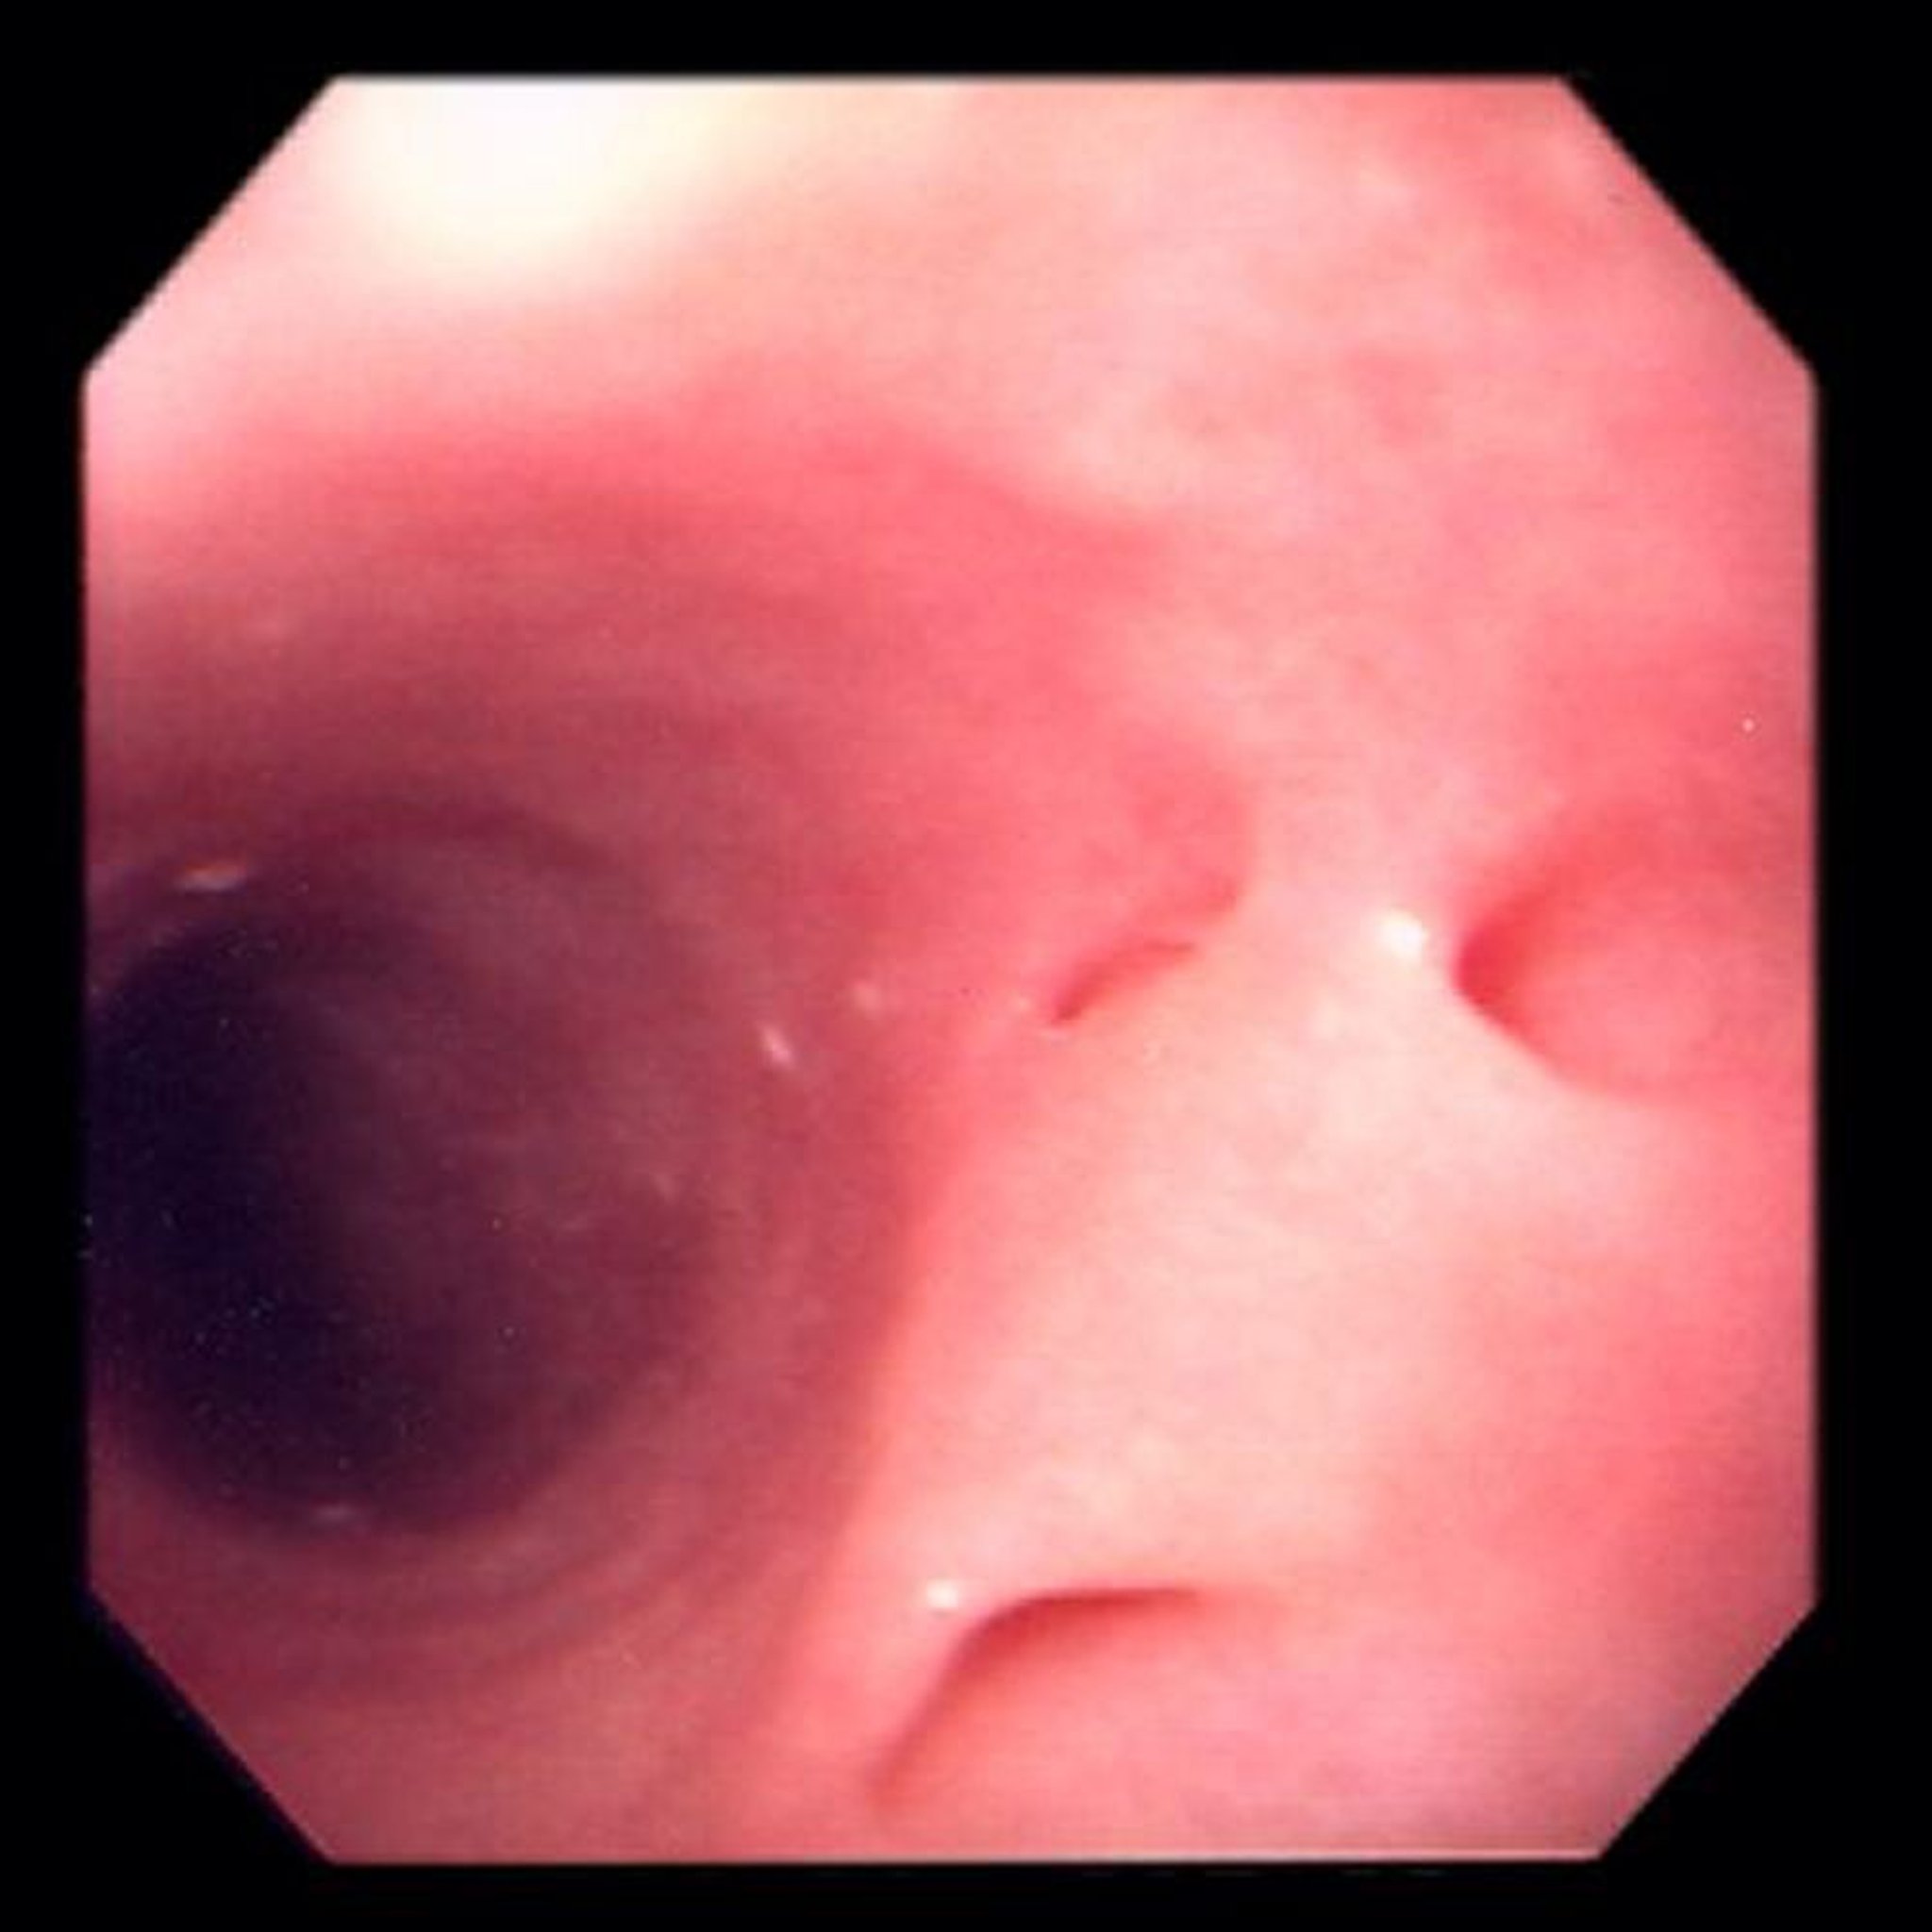

Essa fotografia mostra pequenos divertículos (setas) na parte superior do esôfago.

Fotografia fornecida pelo Dr. David M. Martin.